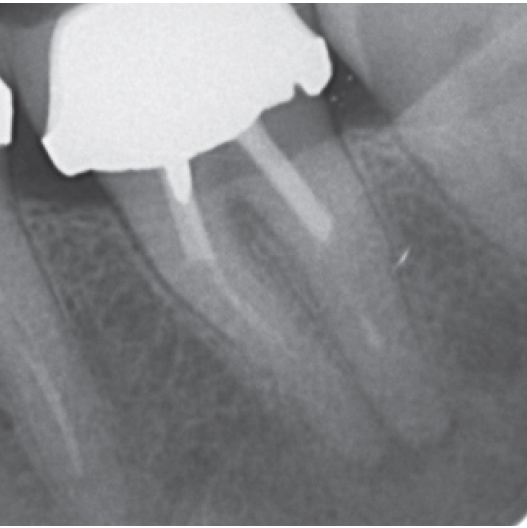

After

After Root Canal treatment